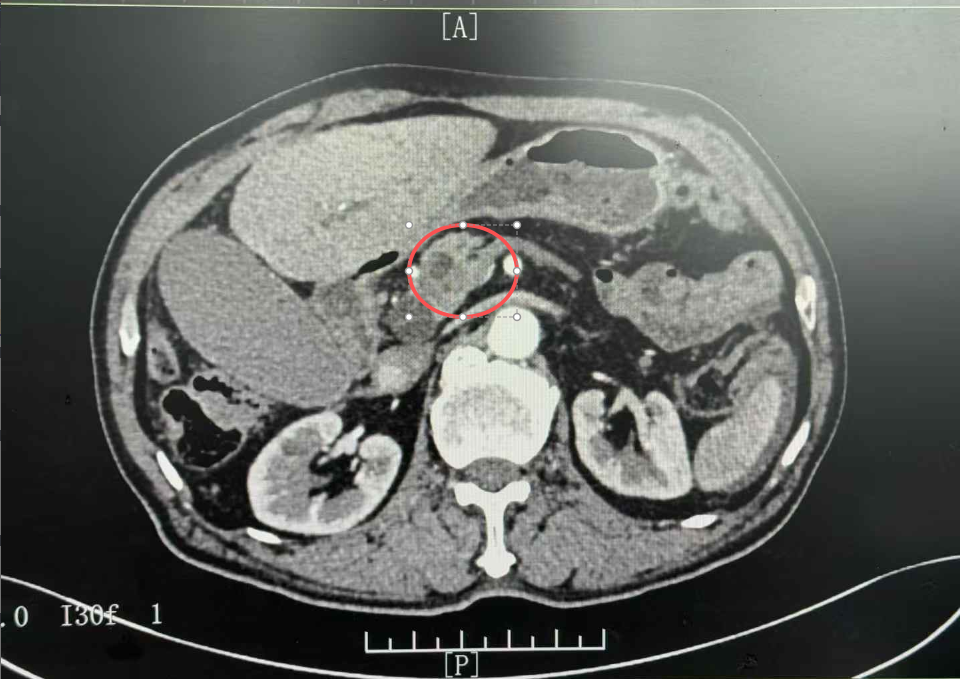

经系统检查,李主任凭借着丰富的临床经验迅速指出,海伯的胰头部占位考虑为胰头恶性肿瘤,同时他还伴有肝功能不全、梗阻性黄疸等一系列严重问题。

△胰头恶性肿瘤